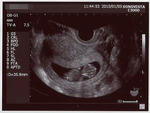

前回の倍の3.6センチに成長。

なんか劇的にでかくなった気がする!子宮の中いっぱいになってきたw

因縁の6週目を無事超え、7週目突入! と思ってたら、

先生に「この大きさは8週目だね」と言われるw

予定日も一週間縮まって、8月1日になりましたw